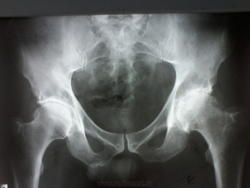

Мужчина лет 50-55, жалобы на боли в т\б суставах около 2 лет, выпоняли Р-гр около года назад, написали коксартроз, отправили лечиться. Сейчас опять боли стали беспокоить. Что скажете, уважаемые коллеги, как описать ?

Артрозоартрит 3-4 ст. по Келлгрену с кистовидной перестройкой сочленяющихся костей бы написал. Бурсит бы добавил, кэп-импиджмент до кучи - а как же, сейчас так всегда.)  А правый сустав как же - двусторонний же процесс - куда-то пропал?

Я наверное к старости слаба глазами стала.Ограничилась бы коксартрозом справа IIст., слева - III ст. (по Косинской), без "-ита", и тем белее без а.некроза.

Что поделать, пишите "асептический некроз". В Азии его пишут: "... Primary OA is the most common diagnosis for THA in studies  from  Europe,  USA,  and Australia,  while  FHN  has  been the most common diagnosis in several studies reported from Asia" - Acta Orthopaedica 2014; 85 (1): 11–17. Ведь, мы же Азия.

Правый сустав теперь я узрел. В нём дела получше. С асептическим некрозом коллеги я не согласен. Но решение Ваше, а моё только мнение,.. никчёмное.)

Не согласен с некрозом я потому, что фонит для него костная ткань совсем слабо, безо всякого склероза и отёка. Разрежение есть её, и предполагаю артритоартроз потому.)

Спасибо всем, написала деф.артроз, асептический некроз не поставила